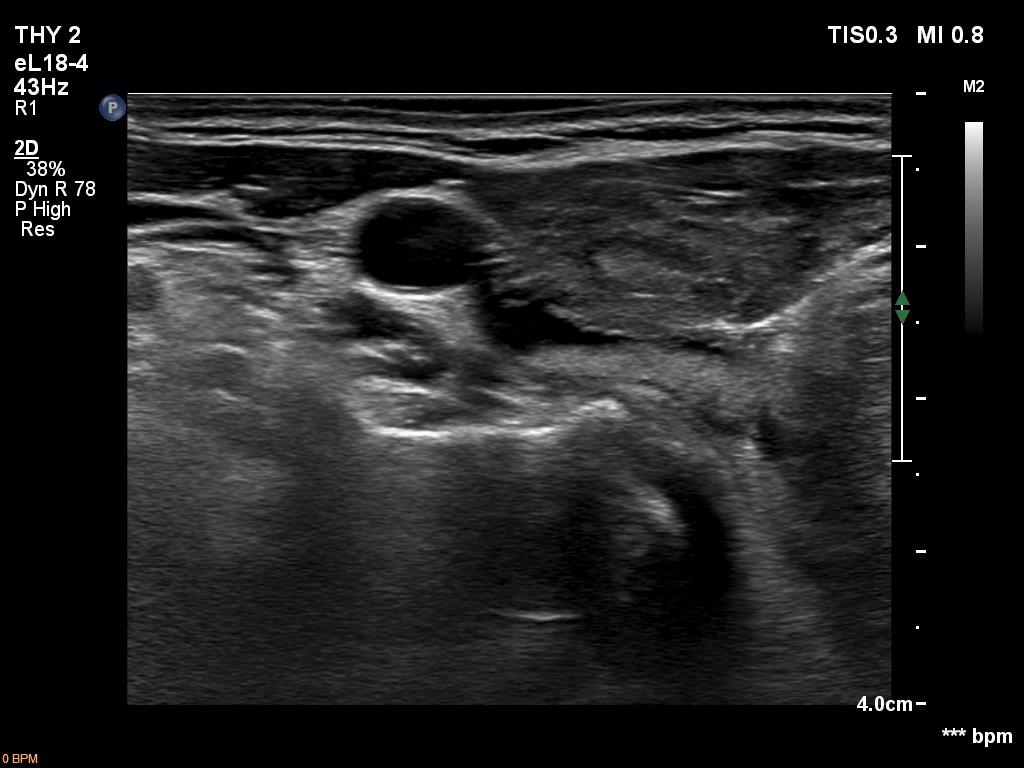

Ultrasonography. The thyroid was hypoechoic and presented several more hypoechoic and echonormal islets corresponding to the underlying thyroiditis. There was a mixed, dominantly cystic mass dorsal to the lower two-third of the right lobe. The lesion has echonormal solid part and showed intracystic echogenic figures.

On ultrasound-guided aspiration 2 mL light yellow fluid was aspirated and cytology resulted in cystic fluid only category.